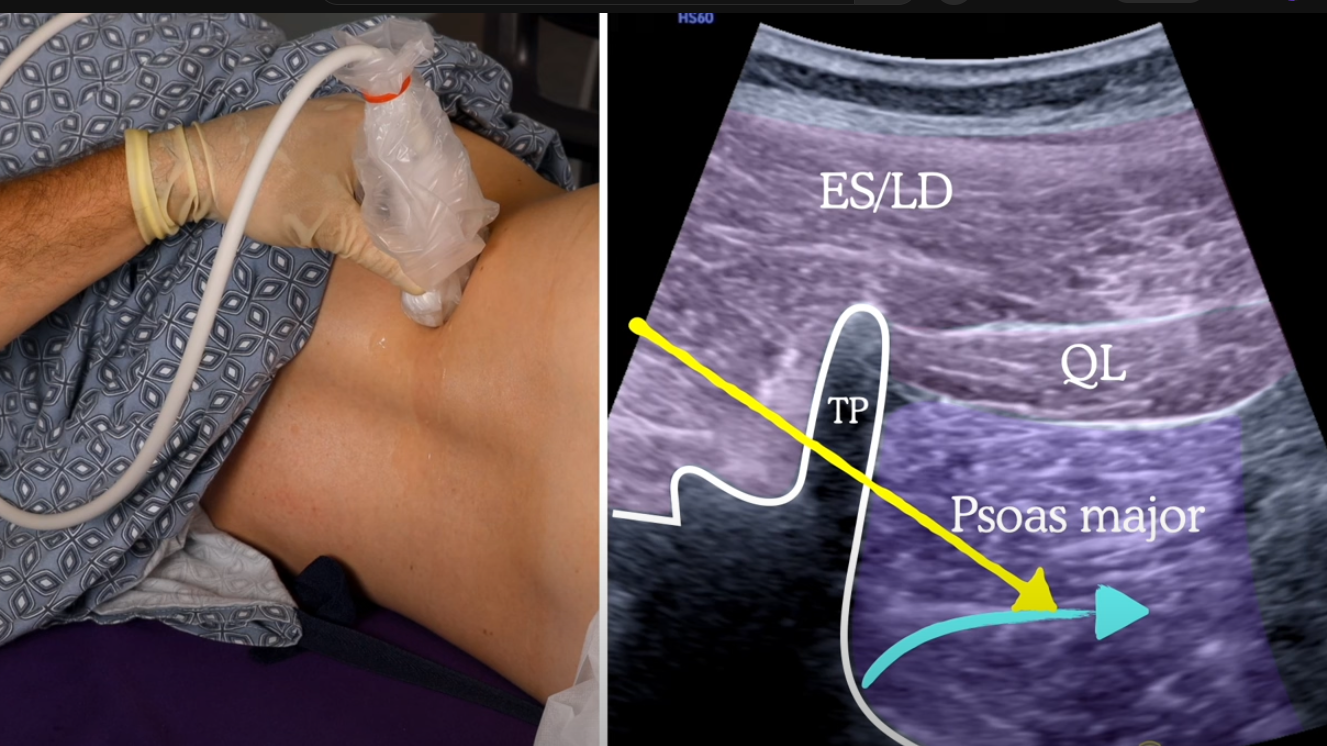

Quadratus Lumborum Block

A

30 mL each side should block most of anterolateral abdominal wall

Curvilinear probe transverse just cephalad to iliac crest

Hip flexed

Needle medial to lateral

QL approaches

Lateral similar to TAP

Posterior: fascial plane posterior to QL (hope local spreads anteromedially)

Anterior: LA between QL and PM. Most effective/best spread cephalad